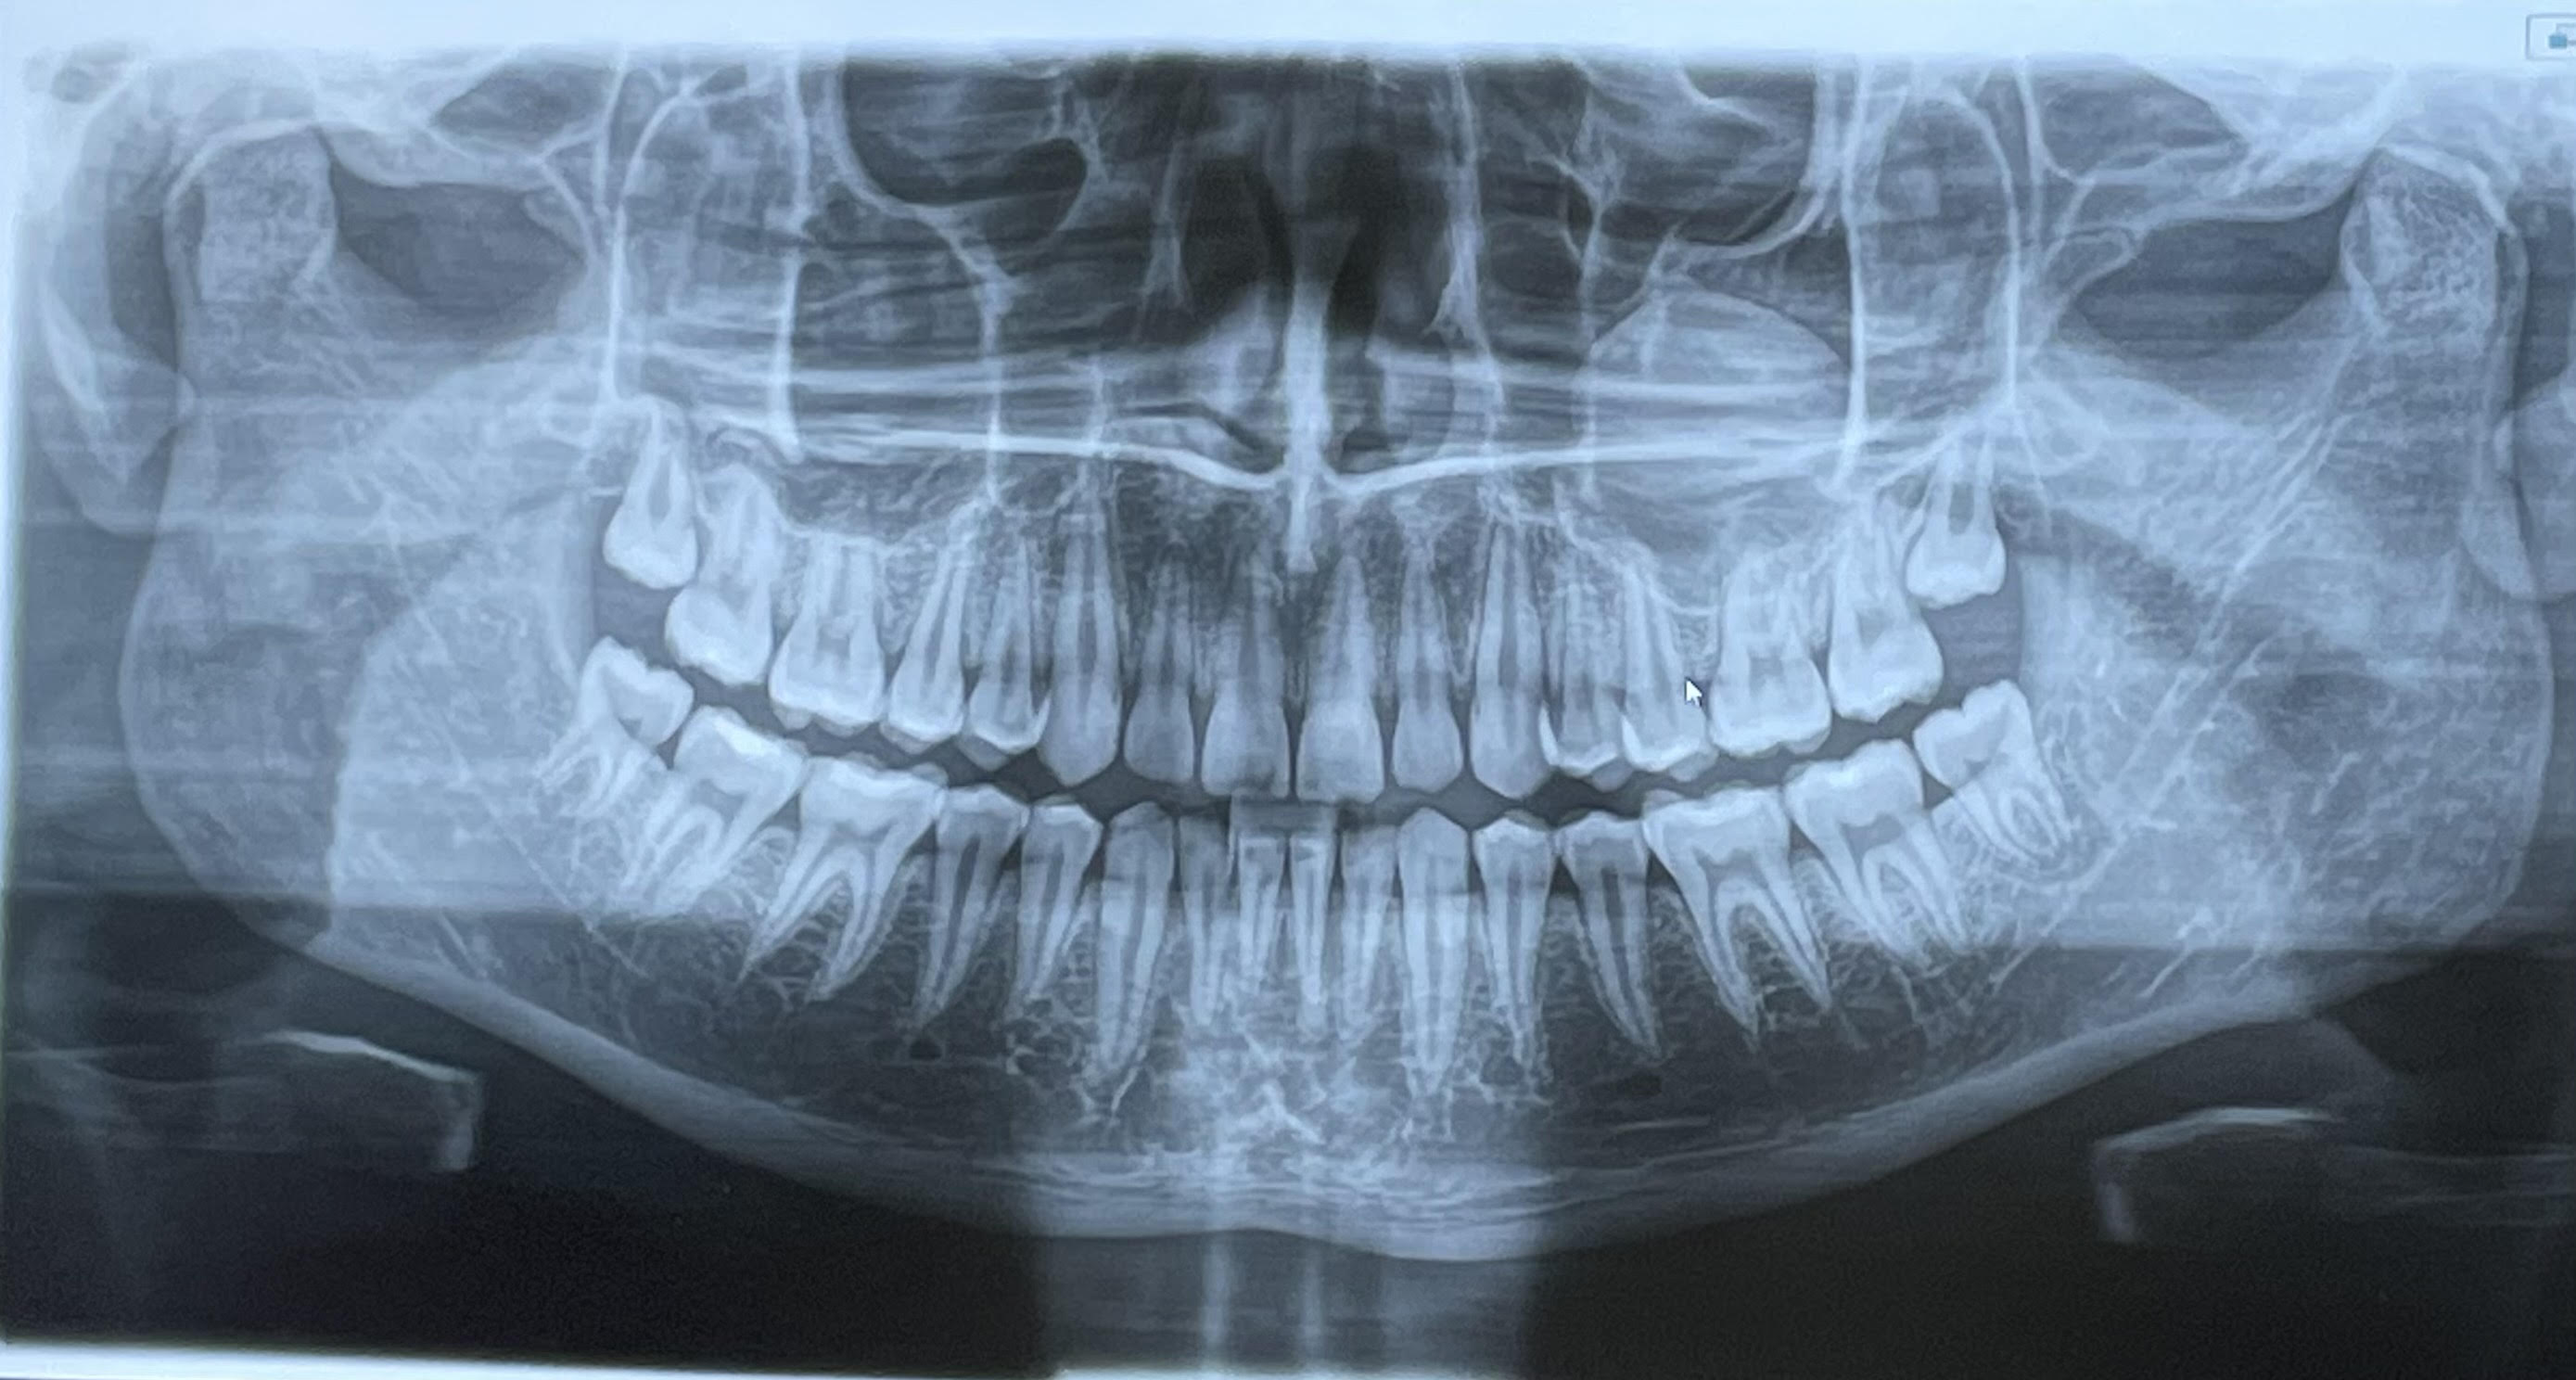

Had this x-ray taken 4 months ago, but I feel no pain in my wisdom teeth. I feel like I have no need to pull them yet, but I don't know.Tell me what you guys think.

No neverHad this x-ray taken 4 months ago, but I feel no pain in my wisdom teeth. I feel like I have no need to pull them yet, but I don't know.Tell me what you guys think.

dont do it unless they start getting super painfulHad this x-ray taken 4 months ago, but I feel no pain in my wisdom teeth. I feel like I have no need to pull them yet, but I don't know.Tell me what you guys think.

Yea I'm super against teeth pulling, but it's a bit scary as the dentist office keeps calling me beginning to get them pulled, telling me it will only get worse, yet I feel no pain.No. Dont remove it. Unless super necessary

My mom said it's good that I'm not getting them removedThey tryna fear monger you jfl. Don't remove wisdom teeth unless they are severely impacted or symptomatic. No rush to pull them and yours have a high likelihood to grow in just fine. Pulling them would cause your 2nd molars to slide back and slight bone reabsorption as no teeth would be stimulating the posterior mandibular alveolar process.

If you are not 18 and your parents are pressing you, I would say you are too scared and want to wait. Do whatever you have to do to save those teeth, it's your life and pulling them will have an impact.